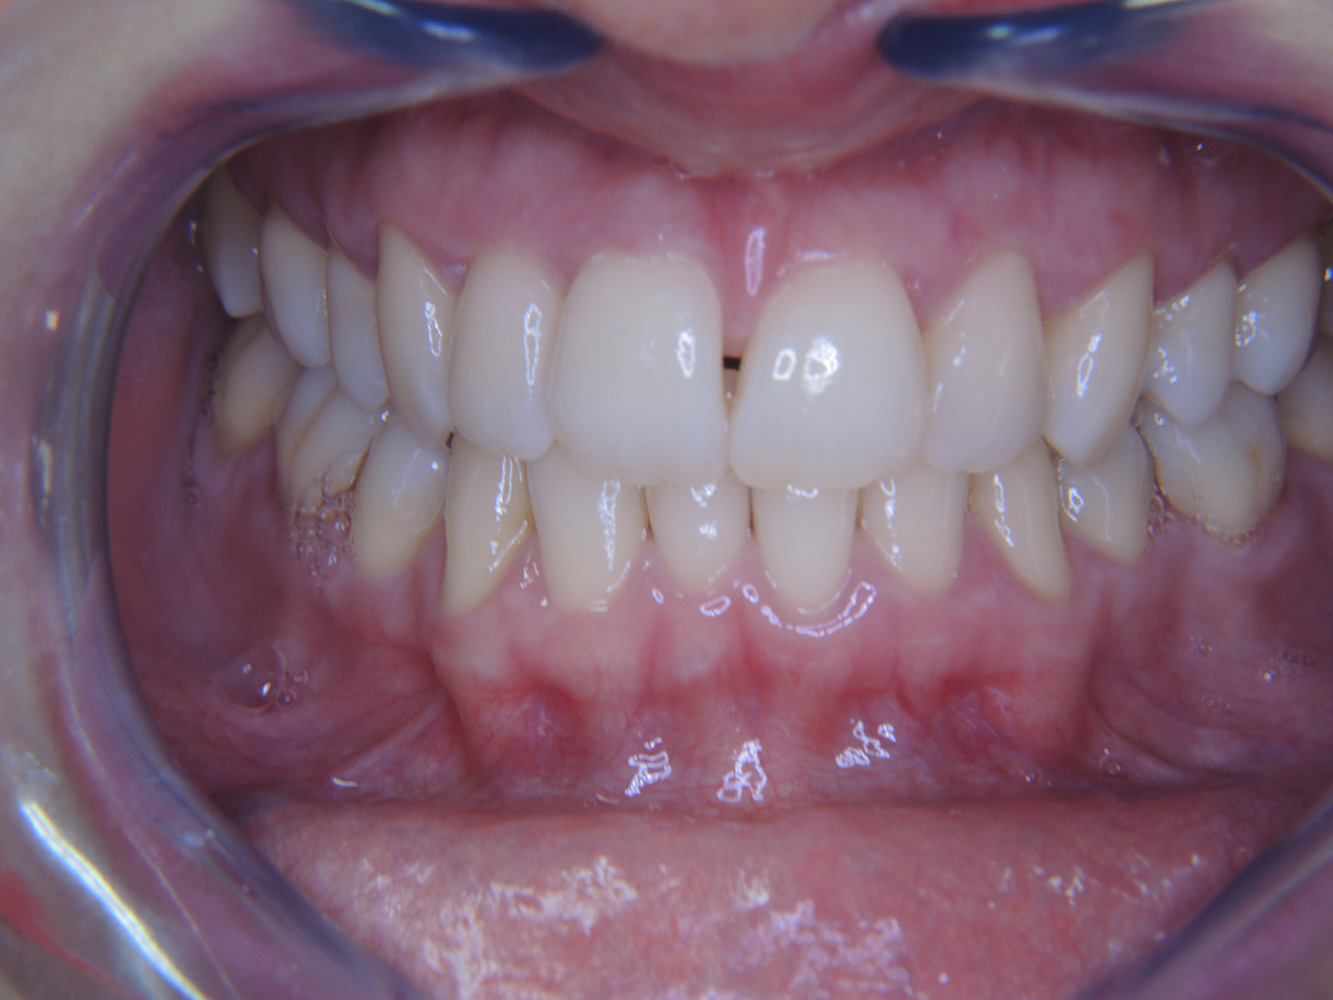

Der gesunde Patient mit parodontaler Vorerkrankung & Periimplantitis

Ein 52-jähriger Patient stellt sich zur Präventionssitzung vor. Der Patient hat keine Allgemeinerkrankungen und nimmt keine Medikamente ein. Er hat verschiedene zahnärztliche Versorgungen und zudem zwei aktive kariöse Läsionen. Außerdem verfügt der Patient über vier Implantate (2., 3. und 4. Quadrant). Es zeigt sich eine parodontale Vorerkrankung (Stadium IV, Grad B). Derzeit herrschen stabile parodontale Verhältnisse, lediglich am Implantat regio 36 zeigen sich Sondierungstiefen (ST) von 5 mm. Zudem lässt sich eine Gingivitis feststellen. mehr Infos